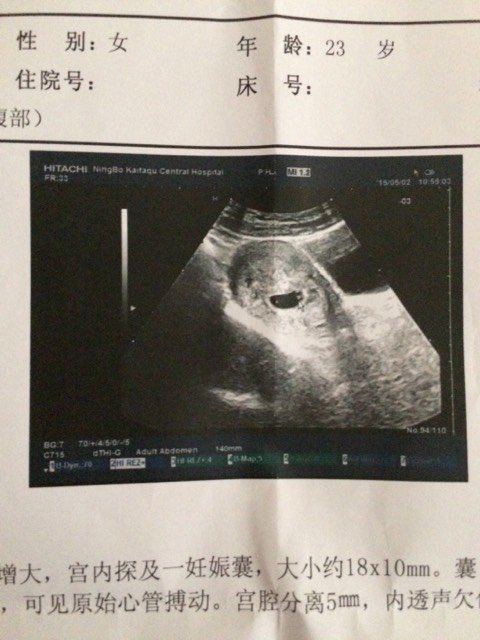

怀孕六周多(45天)昨天五一出去玩走了两三个小时,回家后上厕所发现垫的纸巾上面有一点暗红色的血,今天早上也有一点点,去医院检查做了个B超,医生说有胎心有心跳,但是也不排除流产的可能性,给我开了三盒药(①黄体酮胶丸②胚宝胶囊③维生素E软胶囊)保胎的药,让我要多注意休息,有宝妈跟我情况类似的吗?这个情况严重吗?流产的可能性大吗?【图片是做的b超报告单,下面写的超声所见:经腹探查,子宫前位增大,宫内探及一妊娠囊,大小约18×10mm 囊内探及卵黄囊。探及胚芽组织,大小约3×2mm 可见原始心管搏动。宫腔分离5mm,内透声欠佳。孕囊位于宫体中段稍下。双侧卵巢大小形态正常】超声提示:宫内早孕。宫腔积液。